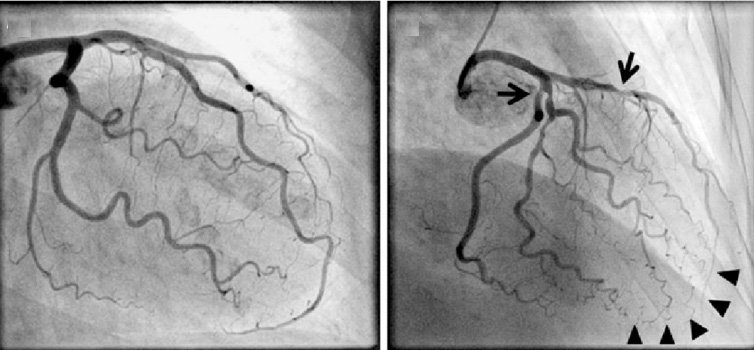

Chụp ĐMV qua da — Ở những bệnh nhân không có dấu hiệu hoặc triệu chứng gợi ý BMV, chúng tôi không khuyên bạn nên sàng lọc bằng chụp động mạch vành xâm lấn. Chụp mạch vành có thể được xem xét ở những bệnh nhân chọn lọc cần sàng lọc BMV nếu các phương thức sàng lọc khác (ví dụ, xét nghiệm gắng sức và / hoặc Chụp mạch vành CT) đã mang lại kết quả không chẩn đoán.

Mặc dù chụp động mạch vành từ lâu đã được coi là xét nghiệm "tiêu chuẩn vàng" để phát hiện BMV, nhưng rủi ro khi thực hiện thủ thuật xâm lấn ở một bệnh nhân không có triệu chứng thường được coi là vượt trội hơn bất kỳ lợi ích tiềm năng nào.

goài ra, tính hữu ích lâm sàng của việc xác định các tổn thương BMV tắc nghẽn cao trong dự đoán nguy cơ biến cố mạch vành trong tương lai là không chắc chắn vì chụp động mạch không đánh giá các đặc điểm hình thái và tế bào của tổn thương hoặc ý nghĩa chức năng của nó.